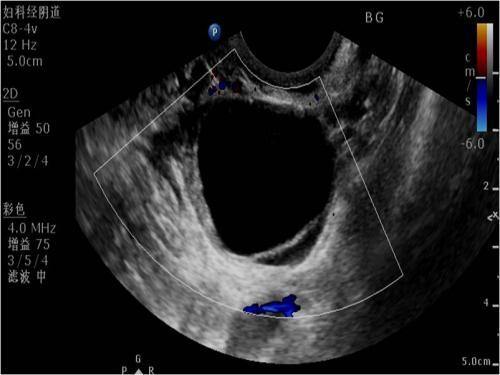

所以怀孕的初期做B超时经常会发现卵巢有囊肿,如果囊肿在5cm以内,医生一般首先考虑妊娠黄体囊肿。这时候卵巢囊肿属于正常的囊肿,到怀孕70天左右,黄体功能慢慢被胎盘取代的时候,妊娠黄体囊肿完成了自己的使命,慢慢的萎缩,消失。